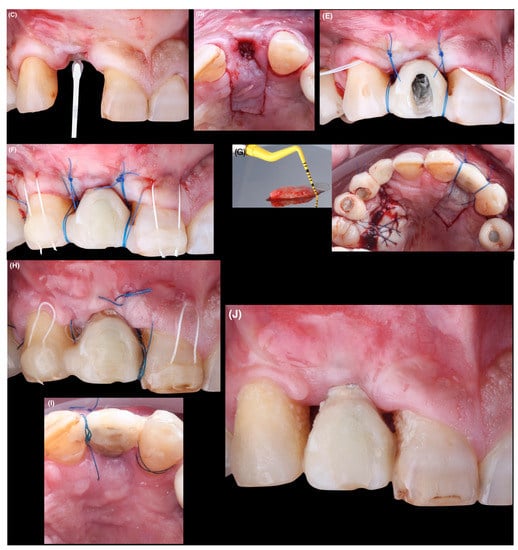

After completing the first phase of treatment, a second surgery was performed 11 months later (Figure 4A,B).

Figure 4.

(A): Before performing the second surgical procedure. (B) Occlusal view. (C): On the buccal aspect a tunneling flap is prepared. Incision is made using a microsurgical blade. (D): Palatal flap design. (E): Subepithelial connective tissue graft is inserted into the mucosal tunnel on the buccal side. (F): The provisional is inserted, double-crossed sutures are placed and coronal traction sutures are fixed with composite. (G): Clinical image of the CTG obtained from the palate and immediate postoperative palatal view. The displacement and elongation of the palatal flap is observed. (H): Postoperative aspect of treated area 14 days after surgery. (I): Palatal appearance after 14 days. (J): Postsurgical wound healing at 1 month. Note poor patient plaque control on adjacent teeth.

The flap design consisted of that proposed by Tinti and Parma-Benfenati []. In the vestibular region, a tunneled flap was made with a micro-scalpel (Spoon Blade No.3, MJK instruments, Marseille, France), through a sulcular incision (from mesial tooth 1.1 to distal tooth 1.3) at partial thickness extending beyond the mucogingival junction, which allowed the mobilization of the vestibular flap without tension (Figure 4C). In the palatal area, it consisted of two vertical incisions and one horizontal incision that were made at partial thickness at different depths (Figure 4D). This design of palatal incisions results in greater elongation and passivity of the flap, allowing greater displacement and avoiding the negative effect on the functional and esthetic outcome due to the coronal displacement of the mucogingival junction, resulting in a reduced width of keratinized mucosa, as well as esthetic irregularities.

A CTG was extracted from the palatal masticatory mucosa and placed in the vestibular tunnel-like recipient bed using Cytoplast™ 3–0 PTFE non-resorbable suture (3–0 PTFE, Osteogenics Biomedical, Lubbock, TX, USA). For this purpose, we used two independent mattress stitch sutures at both ends of the tunnel and, by means of the traction of this suture, the graft was introduced and positioned in the created bed (Figure 4E). Once the graft was inserted, it was fixed in position by coronally tractioning the flap and graft through the double-crossed vertical suspensory suture with Seralon® 5–0 (5–0 Polyamide, Serag-Wiessner GmbH & Co. KG, Zum Kugelfang, Naila, Germany).

The gingival margins of teeth 1.1 and 1.3 were coronally repositioned using stitches anchored with composite resin on the vestibular surface of both teeth (Figure 4F,G).

The stitches were removed after 14 days and the patient was followed up for 7 months to monitor surgical healing (Figure 4H,J). At 7 months, the soft tissues maintained their volume and an adequate gingival profile had been achieved. In addition, the tips of the papillae were also positioned more coronally, so the definitive restoration of the implant was carried out.